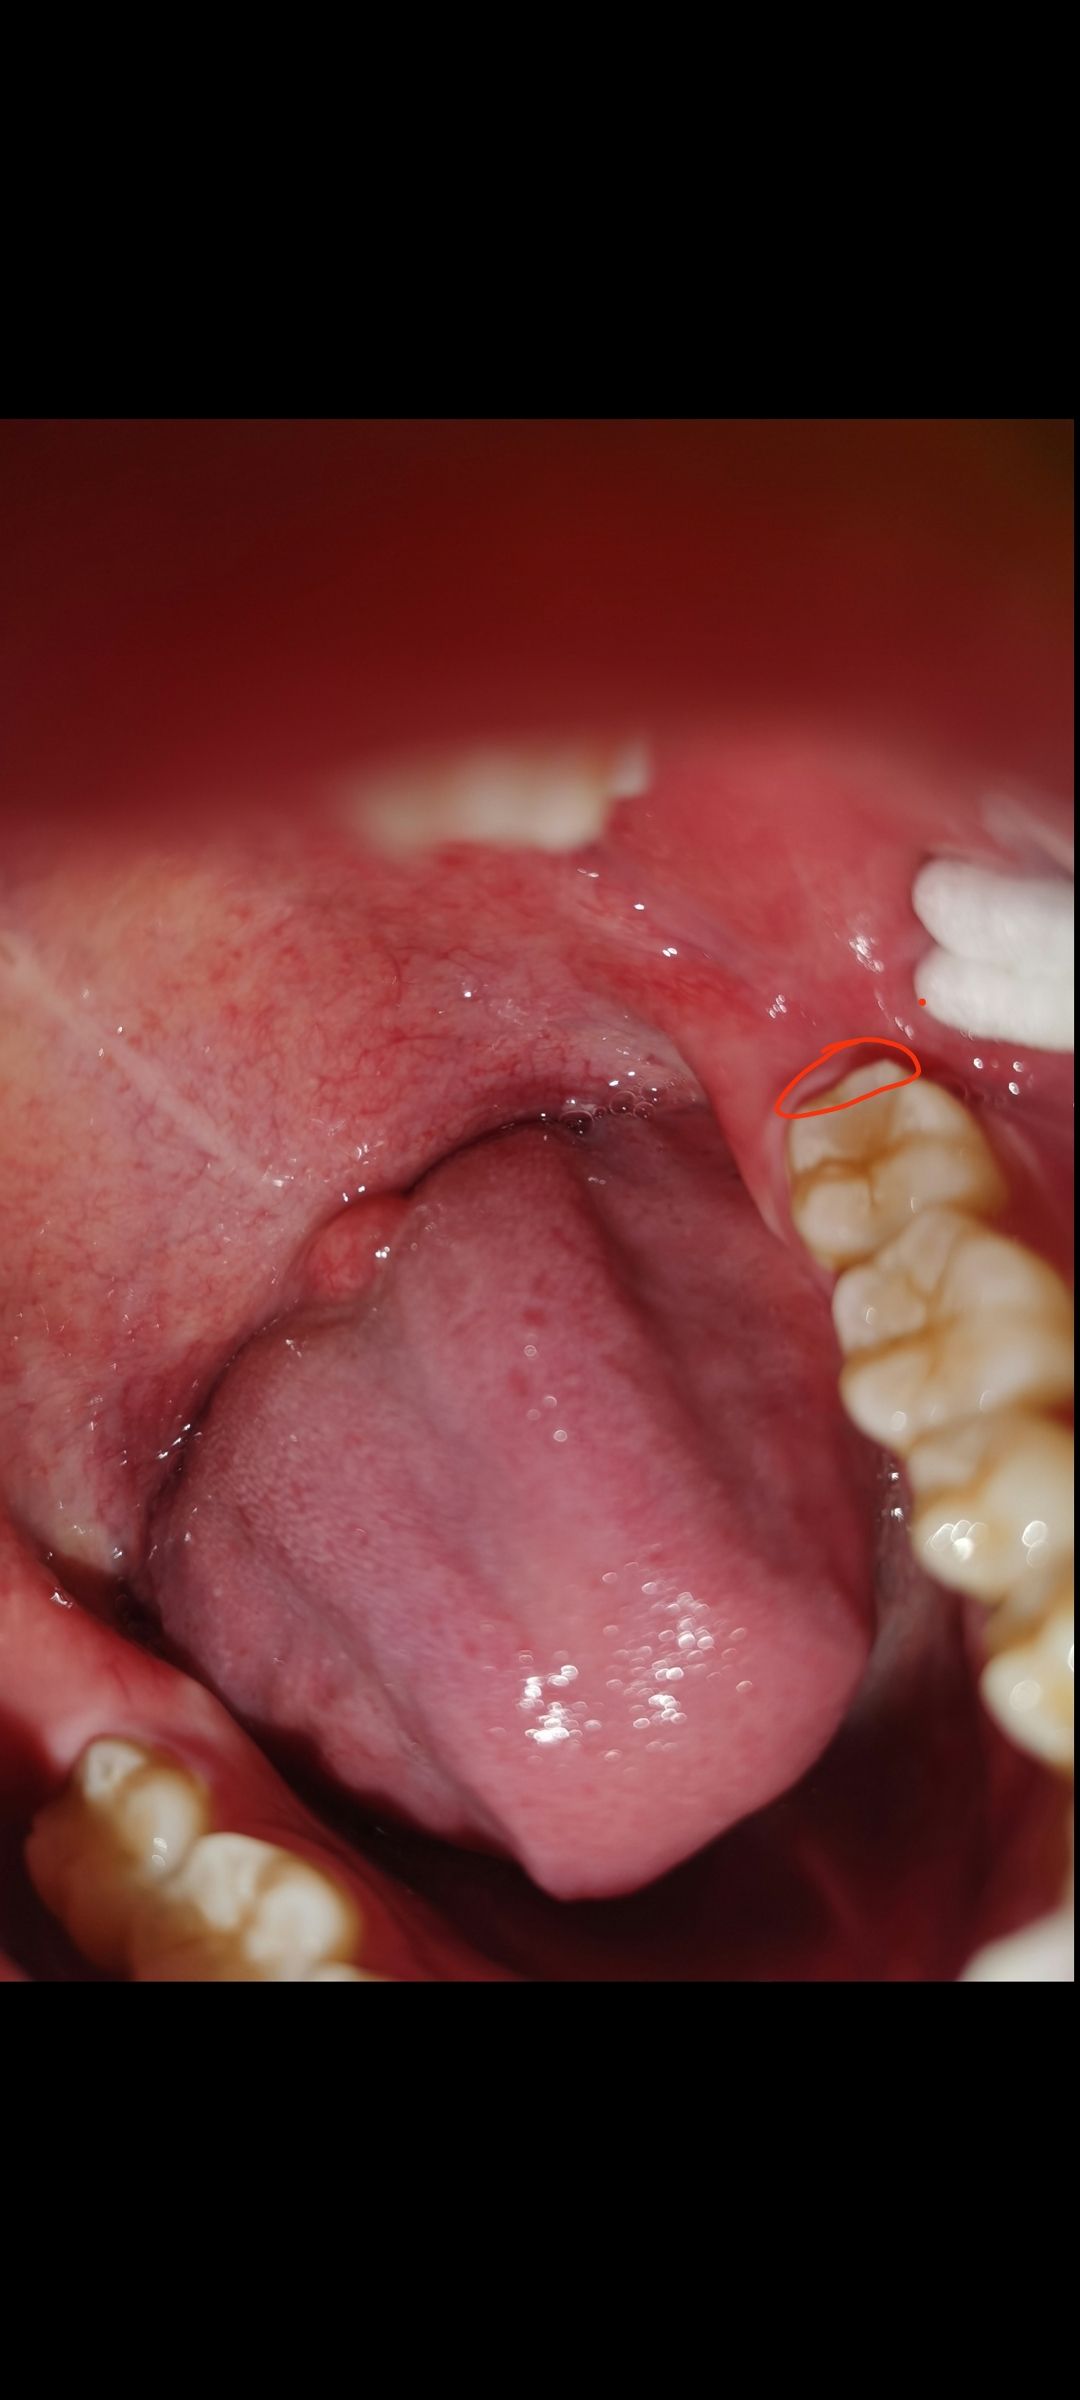

[四川群众呼声] 广安市人民医院口腔科拔完智齿导致邻牙酸疼[已回复] |